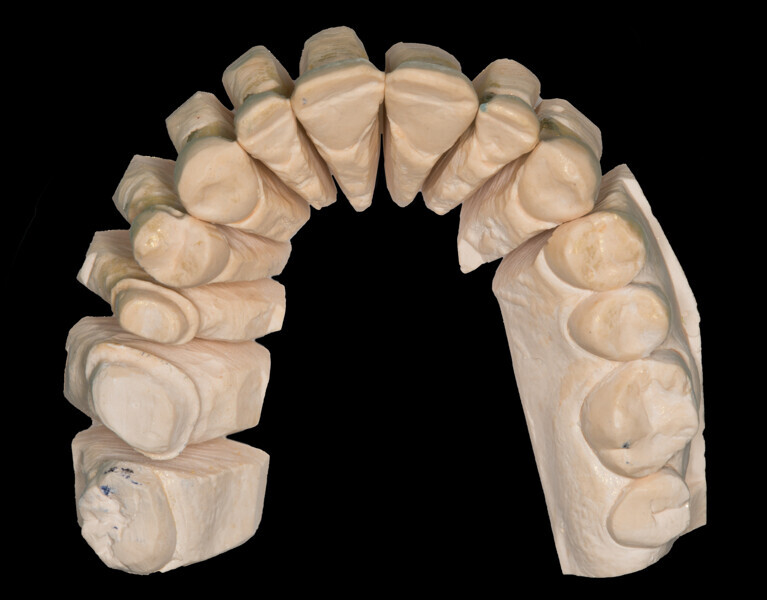

Fig. 16: Final analogue ceramic restorations.

Fig. 17: Final analogue ceramic restorations.

Fig. 18: Final analogue ceramic restorations.

Fig. 19: Final analogue ceramic restorations.